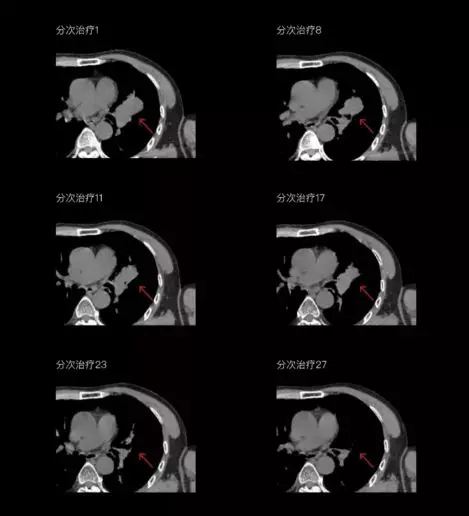

聯(lián)影CT-linac全程監(jiān)測治療過程病灶的變化,及時調整和優(yōu)化治療方案